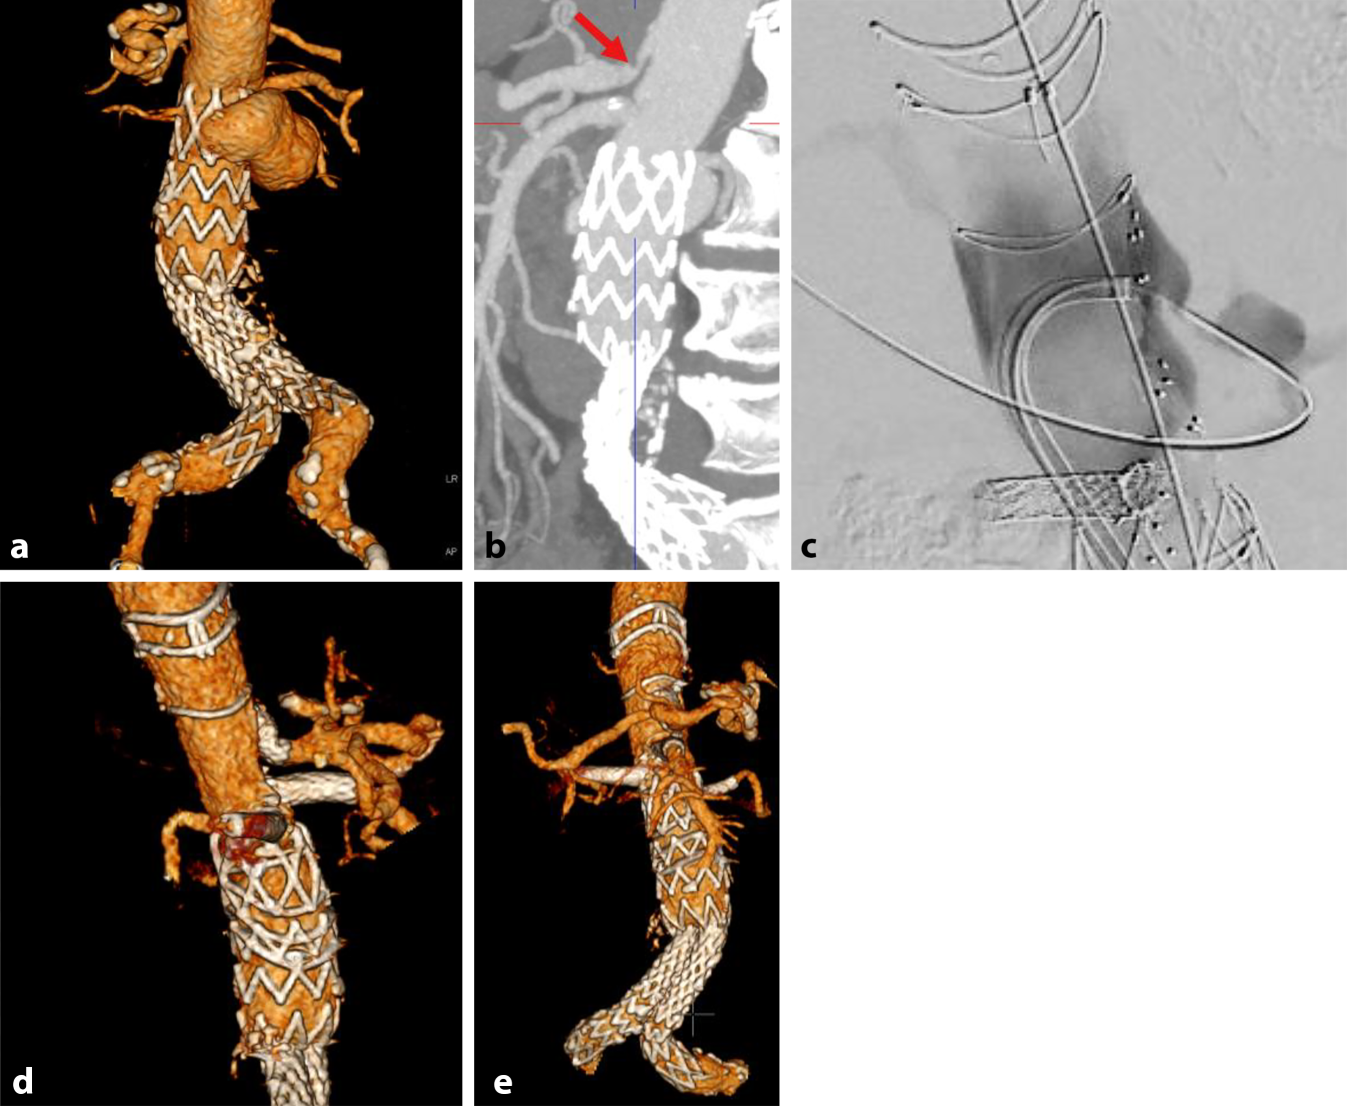

Der Patient (mit hohem Risiko für eine offene Operation) wurde bei einem rupturgefährdeten 6,5 cm pararenalen penetrierten Aortenulcus, 10 Jahre nach EVAR mit zusätzlicher Kompression des Truncus coeliacus (symptomatisches Dunbar Syndrom) und Nachweis einer hochgradigen Stenose (ac) behandelt. Es erfolgte die perkutane transfemorale Implantation eines 4‑fach fenestrierten Cuffs (Terumo Anaconda) mit erfolgreicher Implantation eines 9 mm Beflared (Bentley) Stentgrafts in dem stark stenosierten Truncus coeliacus (d) mittels steuerbarer Schleuse (Oscor NXT, Düsseldorf, Deutschland). Die Rekonstruktion des CTs zeigt eine effektive minimal invasive Ausschaltung der komplexen Aorten- und viszeralen Pathologie mit offenen renoviszeralen Gefäßen (e). Die abdominelle Symptomatik war im Anschluss komplett rückläufig. Pfeil Lokale Kompression des Truncus ceoliacus